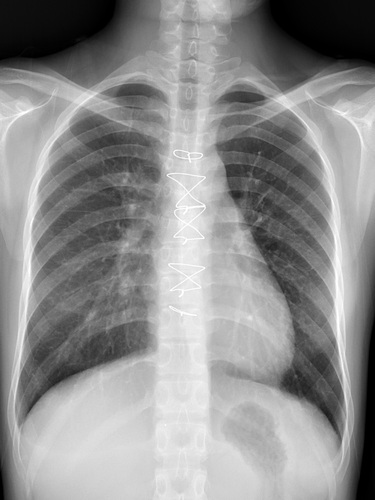

圖:鄭小姐出院後第二次回診檢查,胸部X光影像顯示肺部與心臟已恢復正常。